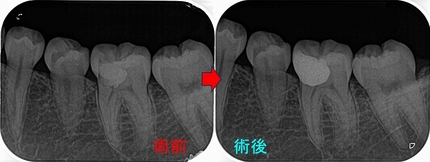

2026 EEdental FUD (3).jpg

この後遠心根抜歯

2026 EEdental FUD (4).jpg

口腔外科で移植をしてもらい、移植歯の根管治療を行い

2026 EEdental FUD (5).jpg

ある程度咬めるように治させてもらいました。

今年になり患者さんが詰め物が外れたとのことで来院

2026 EEdental FUD (6).jpg

10年経過して、そこまで悪い感じはありません。

患者さんにも「先生にそんなに持たないかもしれないよと言われていましたが10年持っています。意外と持つものですね!」と言われましたが、

ホント最初の延長ブリッジの方がかなり良い条件でしたが、折れてしまった。

パフォレーション+分割抜歯、移植した歯という条件の悪いケースで10年経過している。。。

たぶん、私がそんなに持たないかも!?と言った事でかばって咬むようにしているのが

今の状況を作っていると思いますが、ホント術者がどんなに頑張っても咬む力(歯ぎしり含め)で歯は必ず悪くなってきてしまいます。

こういうケースを見ると、患者さんの協力なしで歯を長く持たせることは難しいと感じます。

今回のケースは詰め物のやり替えだけ行えば、またしばらく使うことは可能でしょうd(^。^)